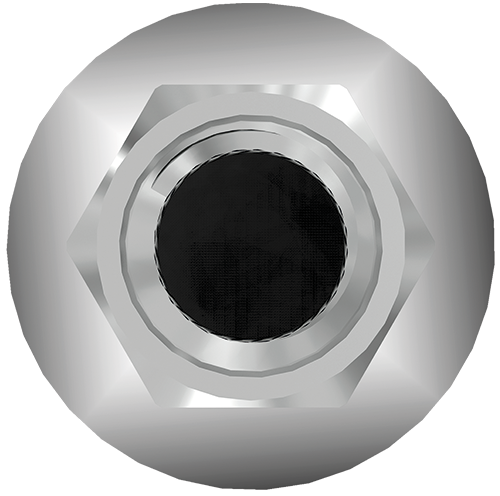

Conexión hexagonal externa universal